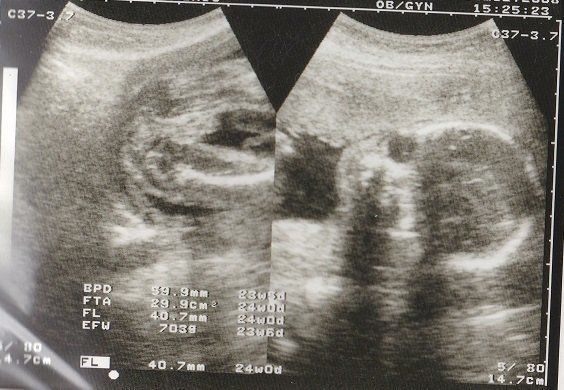

妊娠24週目のエコー写真 早産のリスクがある時期

日常生活が大変な時期になってきました。早産の心配もあるので、重い荷物は持たないようにするなど気をつけました。

右側は赤ちゃんの顔の画像。目鼻も何となくわかって、「ああ顔だなあ」と思えるようになりました。